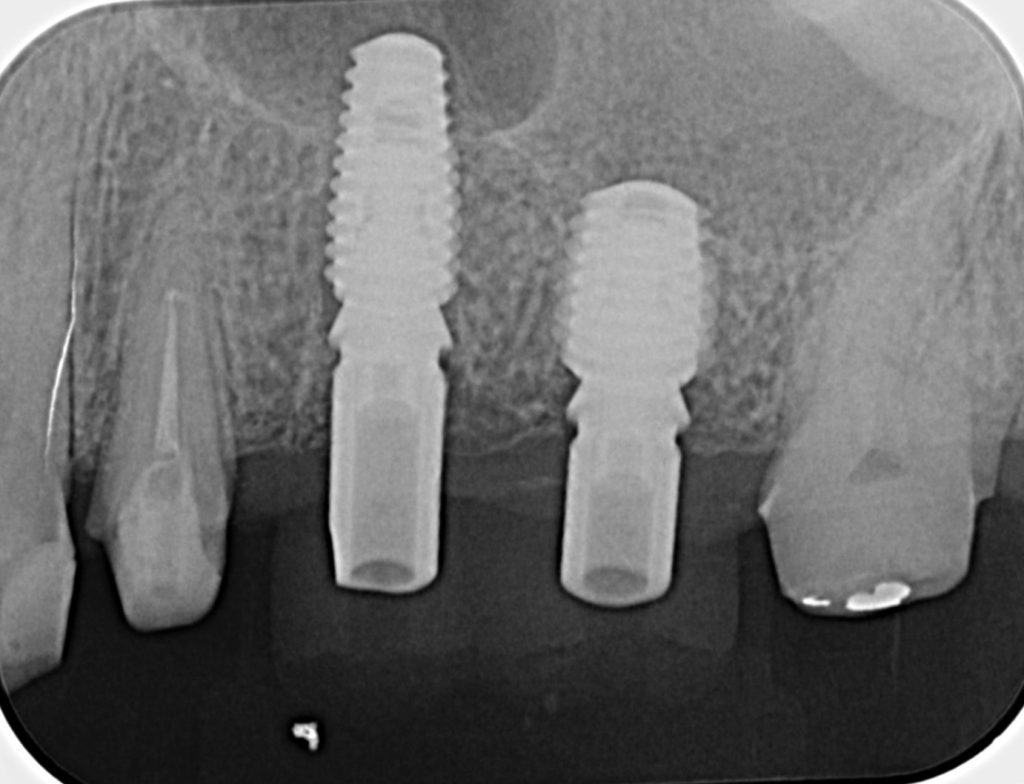

50代、男性、左上に違和感があることを主訴に来院され、インプラント治療を行いました。

| 診断結果 | 左上5番歯根破折 |

| 治療内容 | 抜歯即時インプラント |